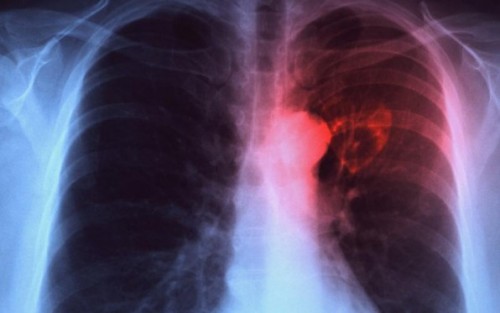

يعتبر مرض السل (التدرن) السبب الرئيسي للوفاة بعد مرض الإيدز حسب منظمة الصحة العالمية. وبفضل التطور التعليمي في المجال الطبي وإيجاد علاجات بالمضادات الحيوية قلت نسبة الوفيات إلى حد كبير.

لكن بفضل نظام الأسد وسياسته بقتل السوريين وحصارهم في عموم مدن وبلدات سوريا والغوطة الشرقية خصوصاً، انتشر مرض السلّ بسبب توفر عوامل وظروف حضانة الفيروس.

أولاً: الحصار مع القصف أجبر الناس على النزول إلى الأقبية، وهو مكان فيه رطوبة لأن الشمس والهواء لا يدخلانه، ويضطر سكان البناء جميعهم للنزول، ويكون العدد كبيراً جداً والمكان صغيراً، وبالتالي ينتقل المرض بين الأطفال والناس.

ثانياً: التغذية السيئة التي فرضها الحصار ساهمت بضعف المناعة عند الناس وازدياد عدد المرضى.

ويؤكد الطبيب أن “القصف المستمر أجبر الناس على السكن في أماكن بعيدة عن الشمس لفترات طويلة، والتعرض للشمس هو أحد أهم وسائل المساعدة للقضاء على السلّ وهذا غير متوفر”.